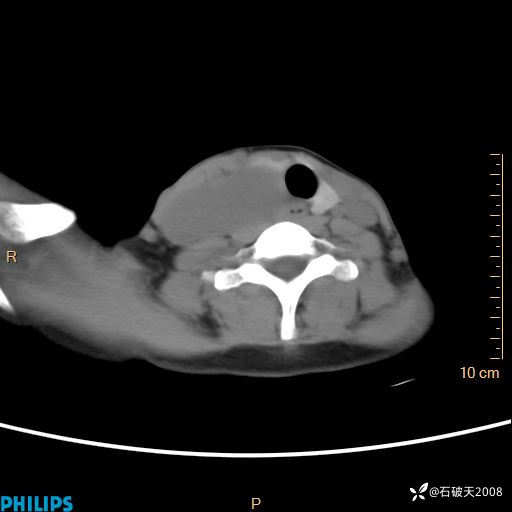

冠状位